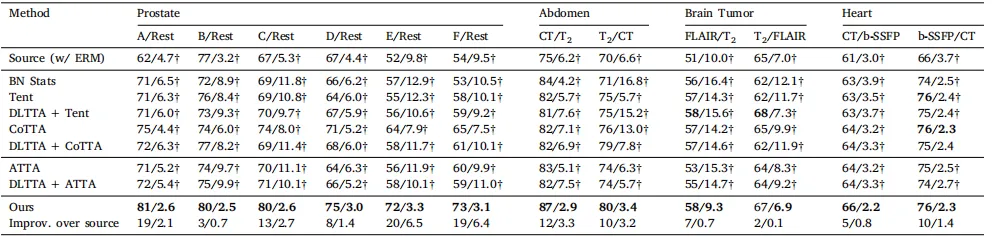

Table 4Quantitative evaluation of benchmarked methods (with ERM source model) on the prostate, abdominal, brain tumor, and heart substructure segmentation tasks. The same sourcemodel was used by all methods. Muscle segmentation was skipped due to the poor performance of the ERM-trained source model (Dice < 8%, ASSD NaN). Results were shownin form of Dice (%)/ASSD (mm). Source and target domains were presented as source/target in the second row. † denotes statistical significance between the Dice/ASSD score ofa method and that of our method (𝑝 < 0.05). Best results were inbold

表 4 使用 ERM 源模型在前列腺、腹部、脑肿瘤和心脏子结构分割任务上对基准方法的定量评估。所有方法均使用相同的源模型。由于ERM训练的源模型在肌肉分割任务上的表现较差(Dice < 8%,ASSD 为 NaN),肌肉分割任务被跳过。结果以 Dice (%) / ASSD (mm) 的形式表示。源域和目标域在第二行中以源域/目标域的形式呈现。† 表示该方法的 Dice/ASSD 分数与本文方法之间具有统计显著性 (𝑝 < 0.05)。最佳结果用粗体标出。